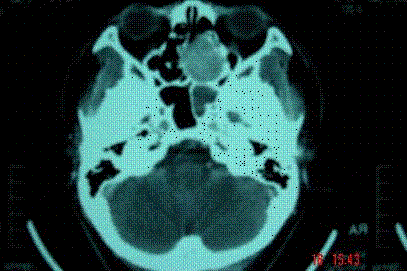

问题 病历摘要: 患者男,37岁,因右鼻塞伴涕中带血4个月入院,患者4个月前始右鼻塞,为间断性,偶有涕中带血,时有流脓性分泌物,并症状渐渐加重。但发病以来患者无头痛、面部麻木和疼痛,无复视及流泪,张口正常。检查:右侧鼻腔总鼻道可见表面光滑、质中、粉红色肿物,触之不易出血。鼻咽黏膜光滑,未见新生物和黏膜糜烂。颈部未及淋巴结肿大。 根据影像学资料,哪几种手术方式较佳? 提示:鼻窦CT显示:右侧中鼻道-上颌窦窦口区见一软组织密度肿块影,大小约35×5mm,增强扫描中等强化。肿块向外侧破坏上颌窦内侧壁突入上颌窦,向内侧破坏鼻中隔累及左侧鼻腔,向上破坏右侧筛窦下壁。右侧中鼻甲骨质破坏。

选项 A、柯路氏进路上颌窦并上颌窦自然开口进鼻腔、筛窦肿瘤切除 B、上颌骨全切除术 C、上颌骨部分切除术 D、鼻侧切鼻腔鼻窦肿瘤开术 E、上颌骨外翻进路鼻腔鼻窦肿瘤切除术 F、上颌骨内翻进路鼻腔鼻窦肿瘤切除术 G、鼻内窥镜下上颌窦内侧壁切除并筛窦、中鼻甲、部分鼻中隔切除 H、面中翻进路鼻腔鼻窦肿瘤切除术

答案 DGH